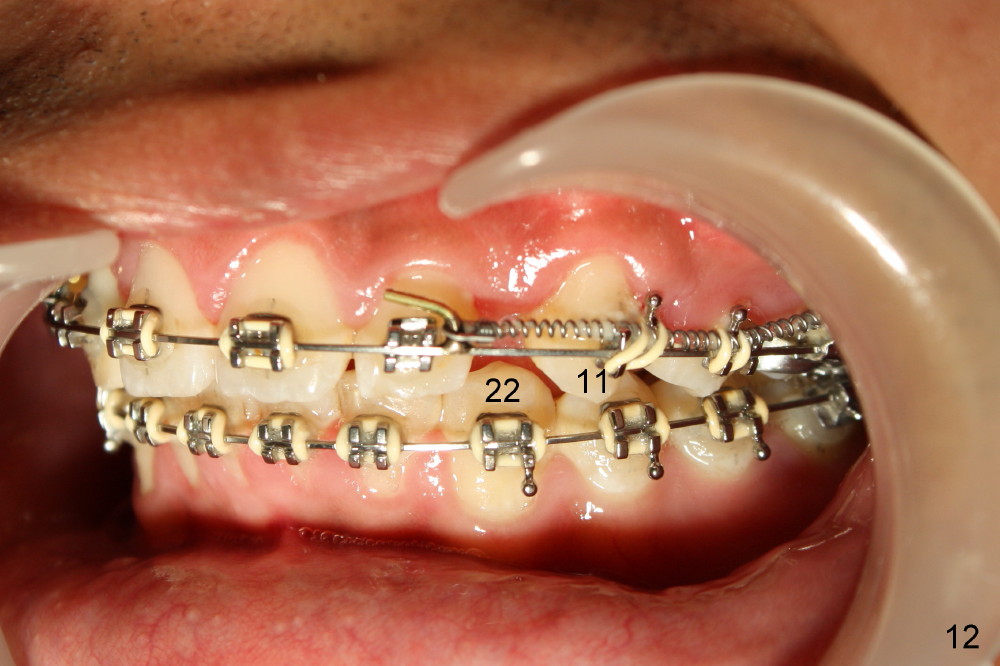

The patient returns 1 month post distalization of the upper incisors (Fig.10-12, 9 months of treatment). Bilateral canine relationship is Class I (Fig.11,12). All needs to be done is to continue distalizing the upper incisors or slightly mesialize the canines if indicated.

Fig.13-15 shows the upper incisors totally 4.5 month of retraction. The upper left canine (Fig.15: #11) seems to be distalized too much, as compared to the dashed line. Therefore whole arch power chain is placed with an intention to bring the canine mesially (arrowhead) while continue distalizing the incisors (including #10 (arrowhead).